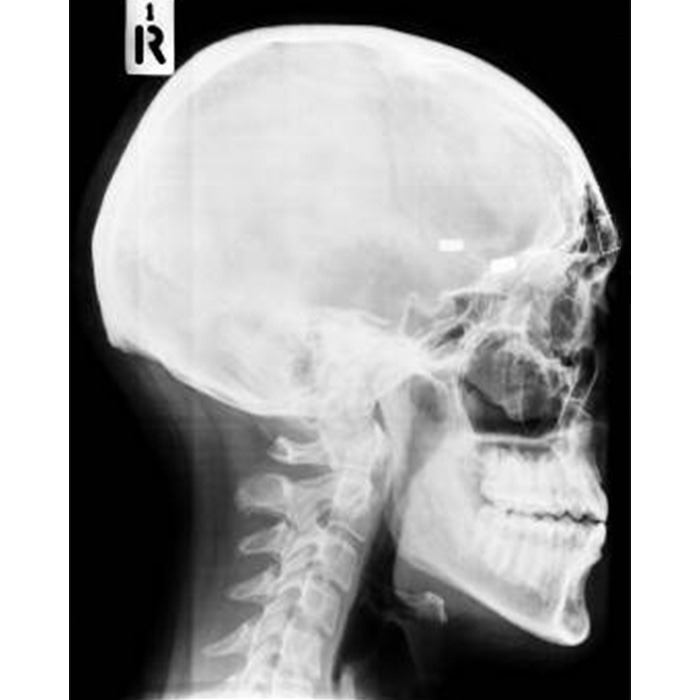

| Before | After |

The procedure for forehead contouring type 3 typically involves making an incision along the hairline. The surgeon will then remove a section of the forehead bone to reduce the size of the forehead. The remaining bone is then reshaped to create a more curved, rounded shape. In some cases, the surgeon may also use a technique called osteotomy, which involves cutting and repositioning the forehead bone to create a more feminine shape.

Once the reshaping is done, the skin is then repositioned over the new bone shape, the incision is closed and the patient is placed in a bandage or a surgical garment to protect the area. In some cases, the surgeon may also use a technique called hairline lowering, which involves moving the hairline forward to create a more feminine appearance.